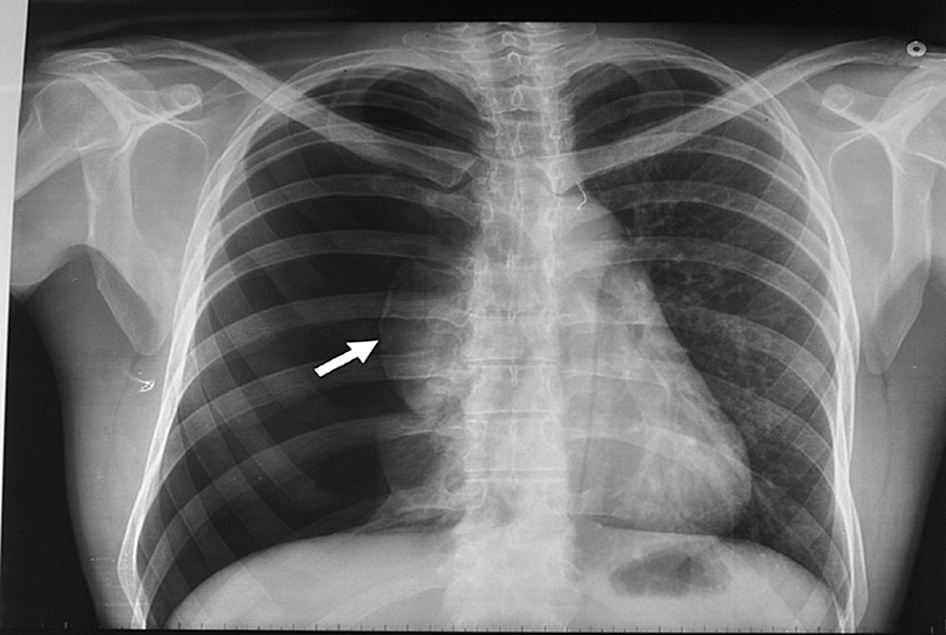

Lancet, 8 de noviembre de 2019    La lesión pulmonar asociada con los cigarrillos electrónicos o el vapeo es una enfermedad emergente asociada con una lesión pulmonar grave y síntomas constitucionales y gastrointestinales. El aumento de la detección ha llevado a la identificación de un amplio espectro de gravedad de la enfermedad en pacientes que fueron tratados con antibióticos y esteroides. A pesar de la mejoría, en el seguimiento a corto plazo, muchos pacientes tienen anormalidades residuales. La lesión pulmonar asociada con los cigarrillos electrónicos o el vapeo sigue siendo un diagnóstico clínico con síntomas que se superponen a enfermedades infecciosas y otras enfermedades pulmonares. Es importante mantener un alto índice de sospecha de esta enfermedad a medida que continúa el trabajo para comprender la causa o causas, la terapia óptima y los resultados a largo plazo de estos pacientes.